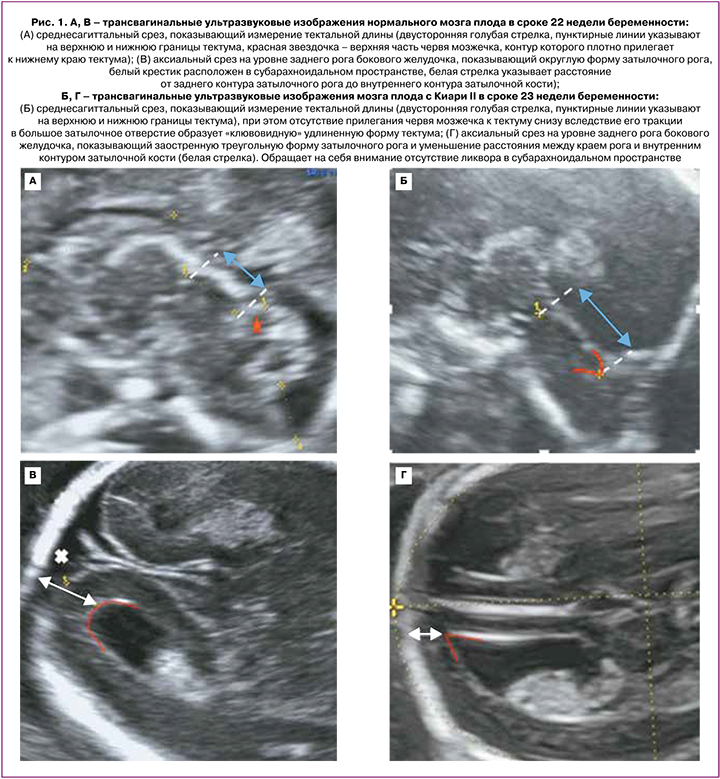

Проанализированы 25 случаев беременности с Киари II у плода. Все беременные прошли перинатальный консилиум на базе ФГБУ «Национального медицинского исследовательского центра акушерства, гинекологии и перинатологии имени академика В.И. Кулакова» Минздрава России в период с января 2019 по февраль 2022 гг. Гестационный срок устанавливался по данным копчико-теменного размера плода во время ультразвукового скрининга I триместра беременности. Плодам проводились: экспертное исследование анатомии, расширенная двухмерная эхокардиография и допплерометрия. При изучении церебральных структур в I триместре беременности оценивались: в среднесагиттальной плоскости – пропорциональное соотношение структур: ствол – IV желудочек – Большая цистерна, в аксиальной плоскости – факт смещения заднего края Сильвиева водопровода к контуру затылочной кости и отсутствие визуализации IV желудочка. При уменьшении расстояния между задним контуром ствола и затылочной костью проводился диагностический поиск уровня спинального дизрафизма. Детальная оценка структур ЦНС со второго триместра беременности включала в себя изучение следующих параметров (согласно нормативным таблицам Timor-Tritsch I. et al. (2012): длина мозолистого тела (расстояние между отдаленными точками колена и валика, измеряемое в среднесагиттальном срезе), его форма, контуры и толщина в проекции колена, тела и валика [12, 13, 17]. Длина тектума (расстояние между максимально удаленными точками верхнего края – точка соединения с задней стенкой III желудочка и нижнего края – точка соединения с верхней поверхностью червя) и его положение относительно ствола мозга (рис. 1).

Во II триместре беременности во всех 20 случаях были выявлены общепринятые эхографические признаки Киари II: вклинение мозжечка в Большое затылочное отверстие с признаком его деформации (форма «банан»), изменение конфигурации костей черепа (форма «лимон»), вентрикуломегалия, наличие спинномозговой грыжи позвоночника. ММЦ и РШ определялись у 15/20 и 5/20 плодов соответственно. Начальный уровень расположения Spina Bifida по отношению к позвоночнику определялся у 2 плодов с позвонка T10, у 14 плодов – с L2–L3, у 4 – с L4–L5 (рис. 3). Средний срок беременности, когда проводилась детальная морфометрия церебральных структур, составил 23,9 (23,0–25,3) недель. Для 20 плодов были характерны изменения: вентрикуломегалия (10–17 мм независимо от уровня поражения спинного мозга), «клювовидный» тектум (крыша мозга), «заостренные» затылочные рога боковых желудочков, задержка формирования борозд (рис. 4, таблица). Средние значения ширины задних рогов боковых желудочков составляли: слева – 11,5 (9–16) мм, справа – 11 (5–17) мм. Дисгенезия мозолистого тела была выявлена у 3/20 пациентов. Для остальных 17 случаев было характерно незначительное укорочение длины мозолистого тела. Средние значения длины мозолистого тела составили 23,8 (14–29) мм (таблица). У половины плодов (55%) определялось дорсальное кистообразное расширение III желудочка. У 3 плодов из 20 с уровнем Spina Bifida L2–L3 была диагностирована межполушарная голопрозэнцефалия. При оценке тектума мы не выявили достоверно значимых различий в его длине по сравнению с нормативными значениями, однако у всех плодов была изменена его форма и расположение. Средние значения длины тектума составили 11,1 (9,5–14) мм. Лишь у 5/20 (25%) плодов длина тектума была более 11 мм, что соответствует более 2 стандартных отклонений для срока беременности 24–25 недель согласно исследованию Leibovitz Z. et al. [12]. У 80% (16/20) пациентов отмечалось нарушение формирования борозд островковых долей при типичном формировании остальных борозд полушарий мозга.

Другой характерной особенностью мозговой организации при Киари II является изменение конфигурации «крыши» мозга – тектума, отвечающего за зрительные и слуховые рефлексы и коррелирующего, по некоторым данным, с выраженностью глазодвигательных нарушений при Spina Bifida [8]. В 2014 г. Leibovitz Z. et al. применили разработанные ими нормограммы среднего (midbrain) и заднего (hindbrain) отделов мозга у плодов с аномалией задней черепной ямки, в том числе с Киари II, и выявили ряд особенностей: удлинение тектума с формированием «клюва» и уменьшение переднезаднего диаметра среднего мозга более чем на 2 стандартных отклонения [12, 13]. В нашем исследовании у всех плодов с Киари II был выявлен «клювовидный» тектум. Однако в большинстве случаев размеры данной структуры не выходили за пределы нормативных значений. Лишь в четверти случаев длина тектума была увеличена и составляла более 12 мм, что выходило за рамки двух стандартных отклонений по нормативной шкале, разработанной Leibovitz Z. et al.